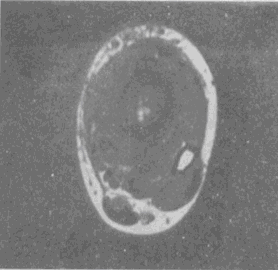

男,33岁,有发热,小腿局部有疼痛,红肿并有压痛,结合图像,最可能的诊断是

男,33岁,有发热,小腿局部有疼痛,红肿并有压痛,结合图像,最可能的诊断是<img border="0" style="width: 324px; height:

[单选题]男,33岁,有发热,小腿局部有疼痛,红肿并有压痛,结合图像,最可能的诊断是A.骨髓炎B.脂肪瘤C.未见异常D.骨髓瘤E.骨化性肌炎

男,33岁,有发热,小腿局部有疼痛,红肿并有压痛,结合图像,最可能的诊断是

[单选题]男,33岁,有发热,小腿局部有疼痛,红肿并有压痛,结合图像,最可能的诊断是A.骨髓炎B.脂肪瘤C.未见异常D.骨髓瘤E.骨化性肌炎

男,33岁,有发热,小腿局部有疼痛,红肿并有压痛,结合图像,最可能的诊断是()

[单选题]男,33岁,有发热,小腿局部有疼痛,红肿并有压痛,结合图像,最可能的诊断是()A . 骨髓炎B . 脂肪瘤C . 未见异常D . 骨髓瘤E . 骨化性肌炎

男,33岁,有发热,小腿局部有疼痛,红肿并有压痛,结合图像,最可能的诊断是()

[单选题]男,33岁,有发热,小腿局部有疼痛,红肿并有压痛,结合图像,最可能的诊断是()A .骨髓炎B .脂肪瘤C .未见异常D .骨髓瘤E .骨化性肌炎